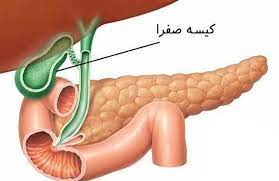

قیمت: 59٬000 تومان - دسته بندی فایل: علوم پزشکی

قیمت: 59٬000 تومان - دسته بندی فایل: علوم پزشکیکبد و مجاری صفراوی (ppt) 51 اسلاید

فروش ویژه پاورپوینت حرفه ای کبد و مجاری صفراوی / تعداد اسلاید: 51 اسلاید